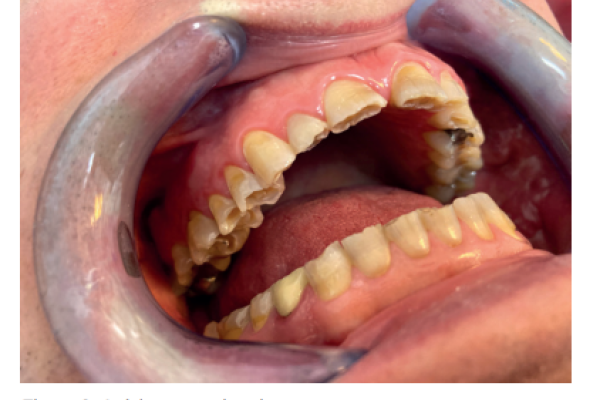

Retención de segundos molares mandibulares: evaluación mediante CBCT y consideraciones terapéuticas ante un caso clínico